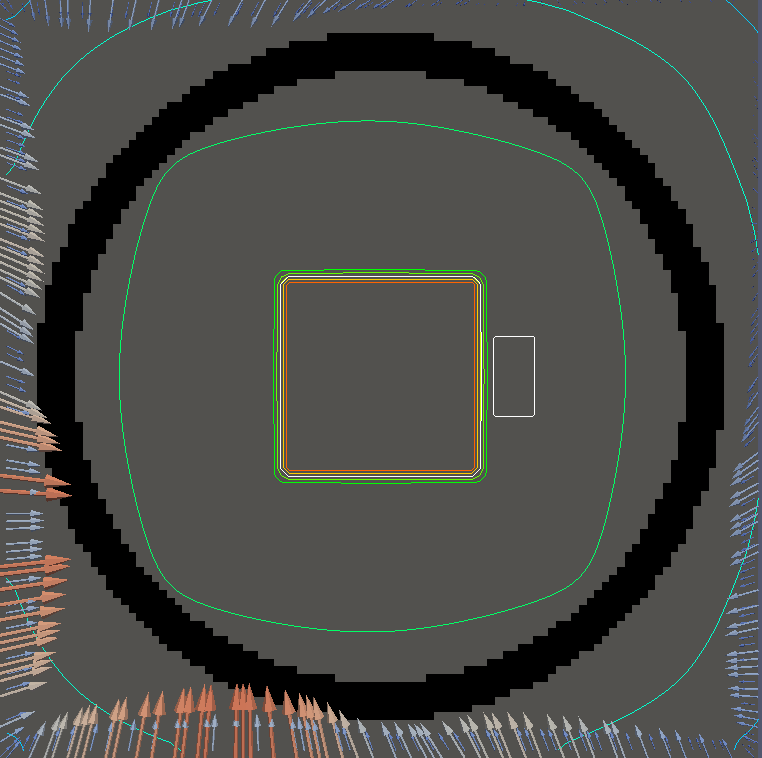

For testing, we use three tumor/risk region regions similar to those in [13]. Specifically, we define the regions in Table 3 and are shown in Figure 1; the void region is shown in black and the tumor and risk regions are traced in white. In the basic target case, seen in Figure 1(a), the tumor region is a box, as is the risk region. The second, intermediate target case, seen in Figure 1(b), involves an L-shaped tumor around a box-shaped risk region. Finally, the complex target case in Figure 1(c) involves a C-shaped tumor around a risk region.

Figure 2 shows the optimal boundary source term for both and The vectors shown on the boundary are the time-integrated values of normalized and then scaled by In Figures 2(a), 2(c), and 2(e) (corresponding to ), the isolines are spaced at intervals of the maximum of the desired dose (here, 5). In the intermediate and tracking cases, we see that relatively low dose levels are attained, primarily due to the high penalty to any dose deposited in the risk region. In Figures 2(b), 2(d), and 2(f)(corresponding to ), the isolines are spaced at intervals of of cells killed. Here a high proportion of the tumor cells are killed (in each case ) while in the Intermediate and Basic cases, the tumor has at least survival; in the Complex case, the risk region has survival.